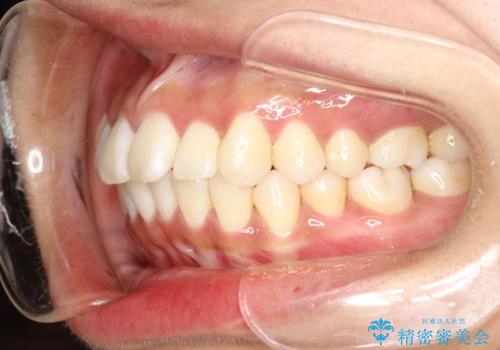

がたがたをインビザラインで整った歯並びへ

- 全体的ながたつきを主訴に来院されました。

抜歯矯正も考えられる状態でしたが、患者様が非抜歯での矯正を希望されたため、歯と歯の間をわずかに削りスペースを作り、全体を整える計画としました。

非常に協力的な患者様でしたので、スムーズに治療を終えることができました。